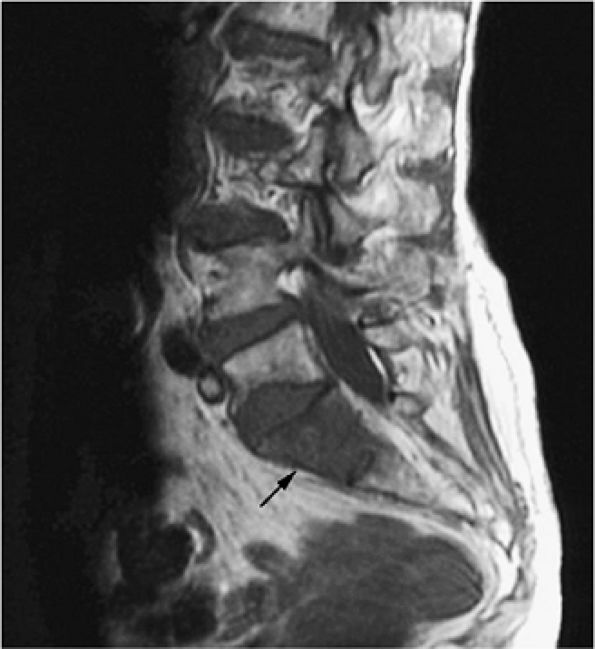

FIGURE 13.34 ● Sagittal T1-weighted image of the lumbosacral spine demonstrates focal low signal intensity of the S1 vertebral body, consistent with lymphomatous involvement (arrow).

|